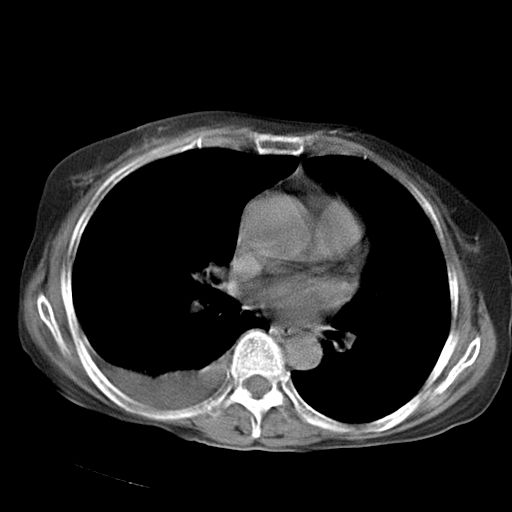

以下是引用jiazh在2006-12-7 20:37:00的发言:[br]肝脏周围半狐形低密度影,肝脏表面受压推移,考虑膈下脓肿可能性大;2、右侧胸腔积液

以下是引用拾荒者在2006-12-7 21:44:00的发言:[br]肝内外胆管多发结石,右膈下多发脓肿,右胸膜腔及叶间裂积液,左肾囊肿。[br] [br]